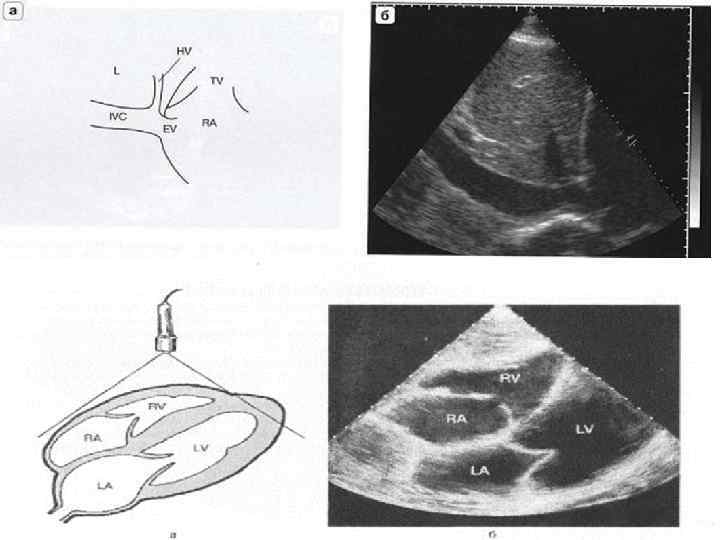

Ультразвуковая анатомия сердца В эхокардиографии используют ряд доступов к сердцу и магистральным сосудам: • Левый парастернальный • Апикальный • Субкостальный • Супрастернальный • Правый парастернальный